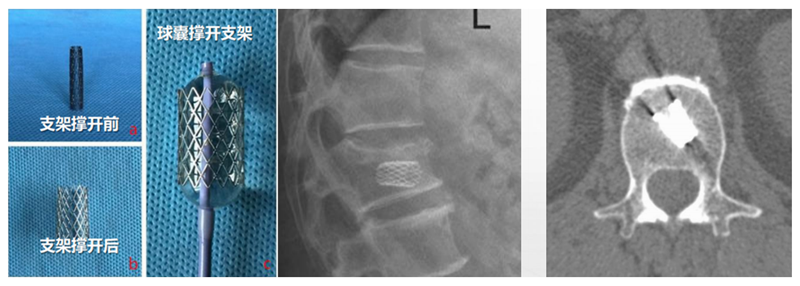

(1)定位与穿刺:透视下确定伤椎椎弓根外缘上1/3 入路点及伤椎上终板或下终板方向并做好标记。由于穿刺容错率高,穿刺针(4. 2 mm)不用过度内倾,不必苛求针尖在椎体内侧壁、后壁位置,穿刺针从椎弓根外缘沿椎弓根方向缓慢穿刺入椎体即可,针尖务必穿刺入椎体后1/3。

(2)弯角导丝开腔:弯角骨钻开腔器械刺入椎体时,注意开腔工具手柄与伤椎终板平行,不要强行开腔,多透视侧位,否则弯导丝可能穿破终板,导致医源性骨水泥渗漏。C形臂X线机正位透视下,导丝到达椎体对侧椎弓根处即可。

(3)弯角骨钻扩张:C形臂X线机正位透视下,弯角骨钻开腔器械螺旋手柄顺时针扭转,让弯角骨钻沿导丝前进开路,将椎体内部钻出弧形通道。操作中注意骨钻沿导丝旋进旋出要完全,旋进不够,后期球囊无法到达对侧,旋出不完全,骨钻会卡在工作套筒上无法拔出。

(4)置入球囊:插入带导丝弯角球囊时注意透视球囊方向,反复调整务必与终板平行。如需要拔出球囊调整方向,务必先拔导丝再拔球囊,透视球囊标记点必须完全从工作套管内出来,否则易造成弯角球囊与工作套管边缘卡磨破裂。

(5)扩张球囊:注入造影剂扩张球囊过程中,注意观察术中正侧位透视图像,控制压力值,不必苛求球囊顶到上下终板,以免发生医源性终板破裂,造成椎间隙骨水泥渗漏可能。注意弯角球囊扩张完毕后拔除顺序:先拔导丝再拔球囊。

(6)注入骨水泥:应用骨水泥灌注管灌注骨水泥时,由聚醚醚酮树脂制成的灌注管在骨水泥灌注完成后要及时拔除,避免椎体内骨水泥硬化后无法拔出;椎体穿刺侧骨水泥灌注不满意,可拔除输送套管,直接连接穿刺套管,进行二次灌注。

术后行影像学检查,显示骨水泥弥散满意,达到了单侧穿刺,双侧弥散的效果,无渗漏